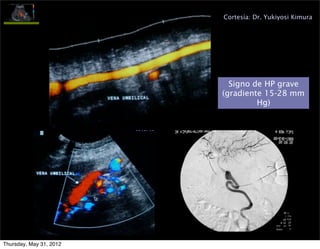

Cortesía: Dr. Yukiyosi Kimura

Signo de HP grave

(gradiente 15-28 mm

Hg)